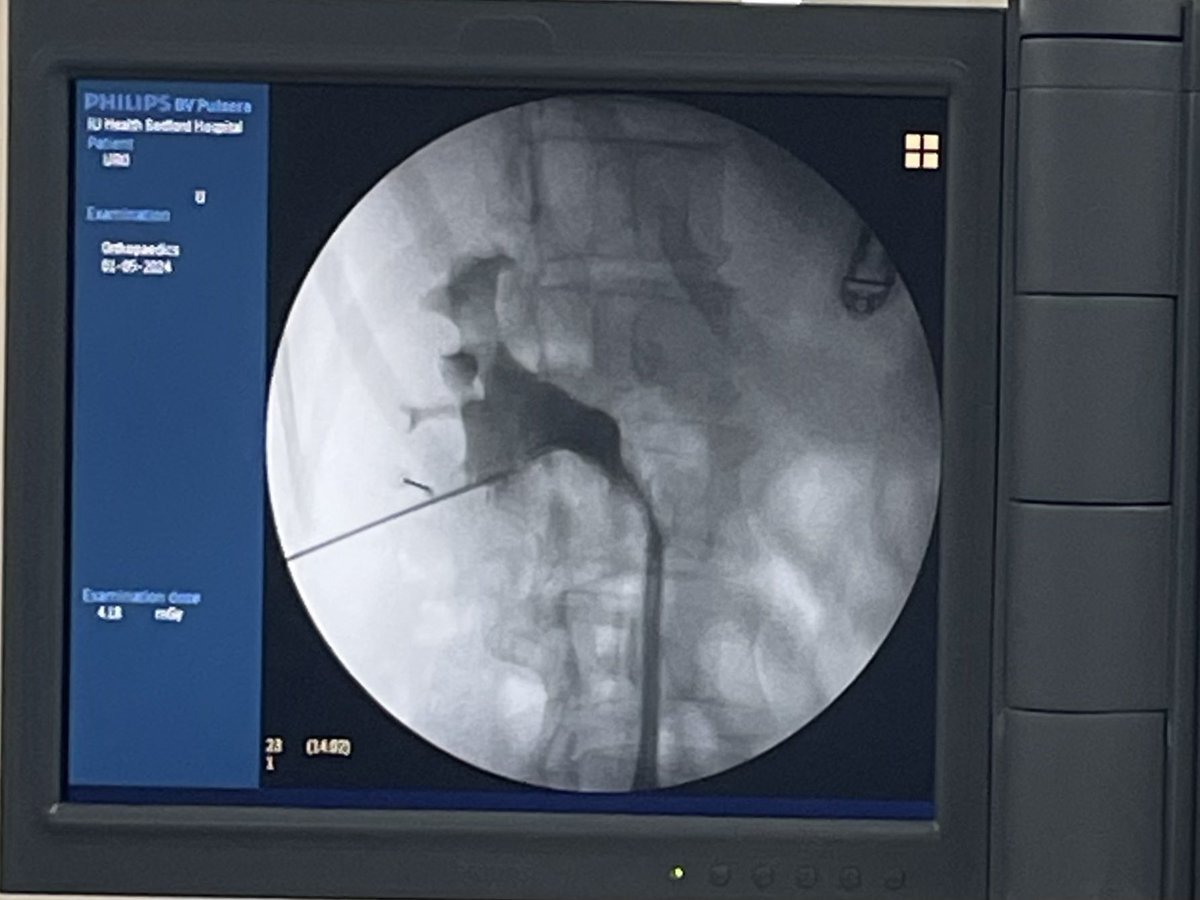

MINIECIRS con técnica biplanar 0-90 modificada, la escuela del Dr @urobraulio en Gdl en el famoso hospital Zoquipan, muchas gracias por la enseñanza y la oportunidad @endourojimenez @endouropat